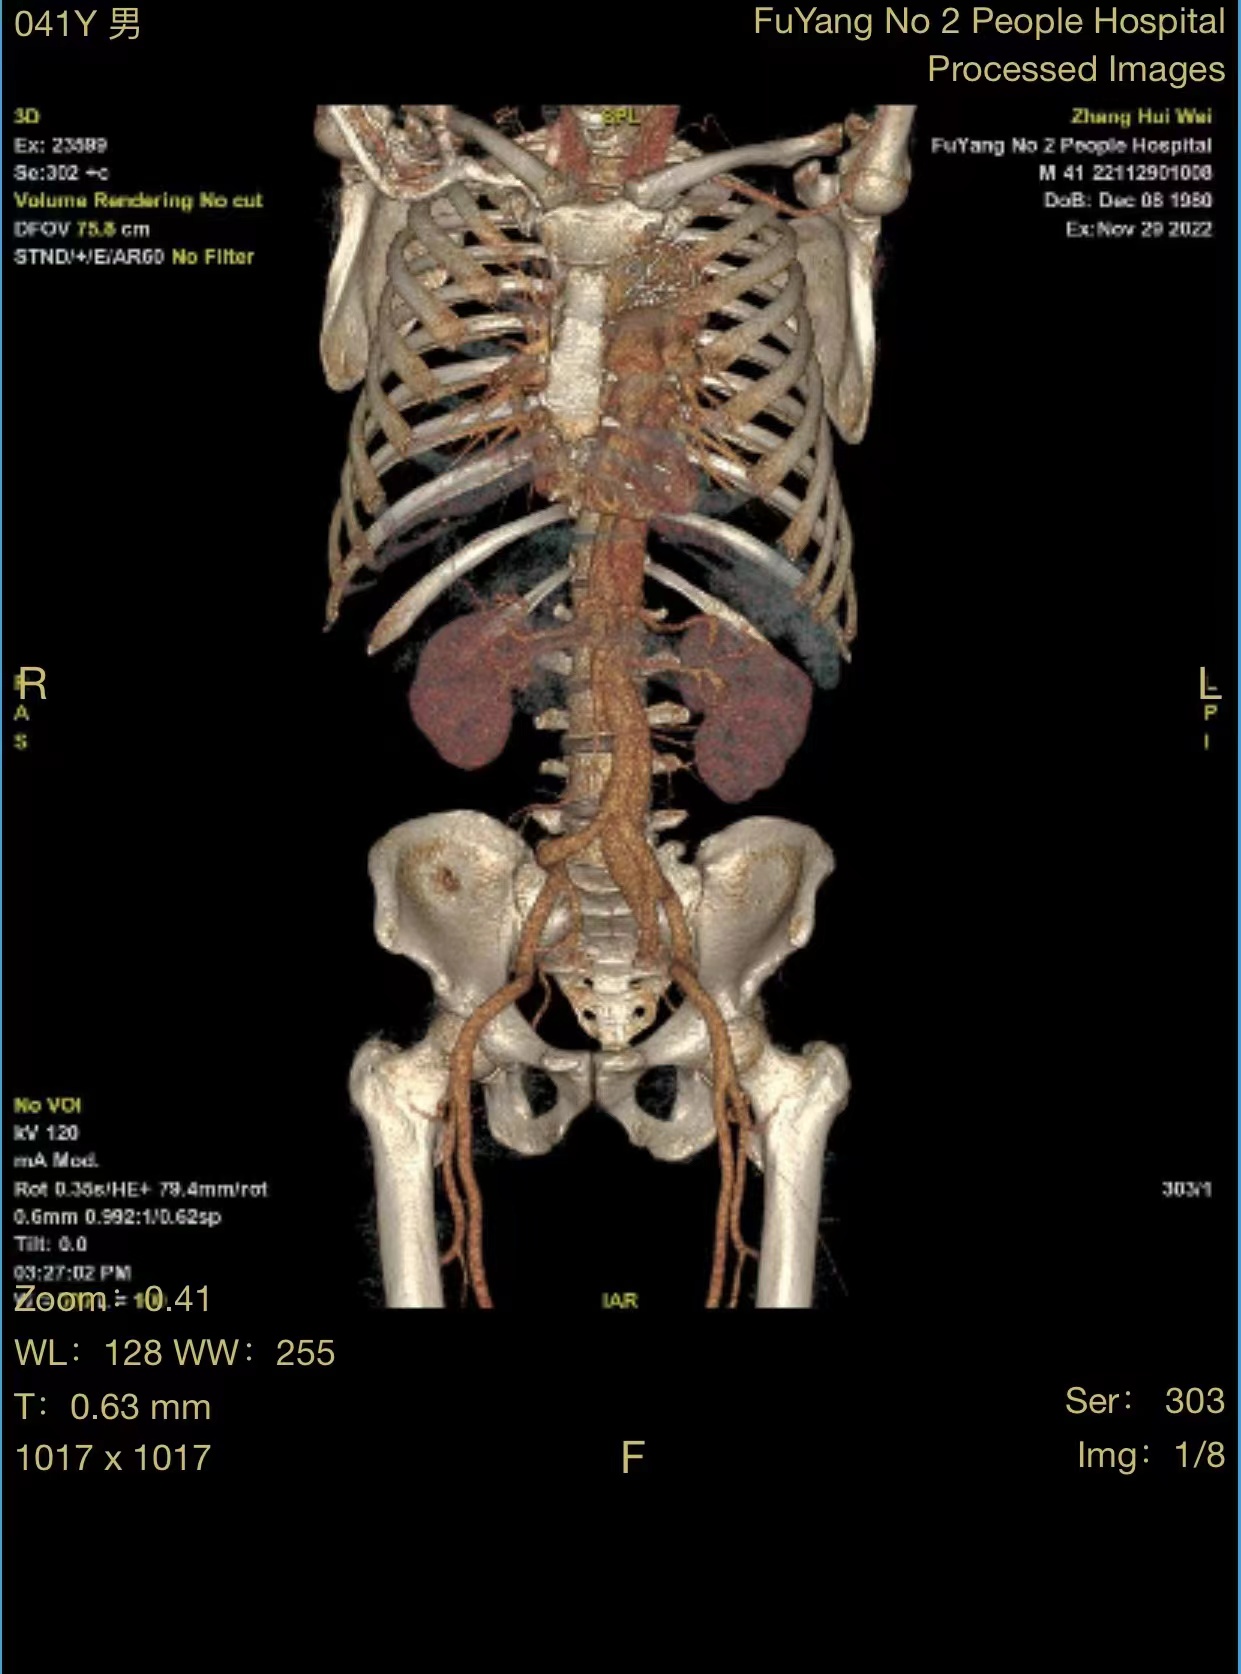

患者张某,男性,41岁,颍州区九龙镇居民,2020年因主动脉夹层在市第二人民医院血管外科行胸主动脉覆膜支架腔内隔绝术,术后恢复尚可,1月前在进行重体力劳动后,出现腰背部疼痛不适,复查主动脉CTA,考虑腹主动脉夹层动脉瘤。

由于患者手术情况复杂,血管外科团队与介入导管室、麻醉科等积极沟通并进行充分的手术准备,在多学科相互配合下,为患者行腹主动脉覆膜支架置入及“四开窗”术,手术顺利,完美隔绝夹层破口,保留腹腔干、肠系膜上动脉、双肾动脉,患者恢复良好。

据市第二人民医院血管外科主任、副主任医师、阜阳市医学会外科学分会血管外科学组组长、血管外科学科带头人芮清峰介绍,累及内脏动脉的主动脉瘤或主动脉夹层一直是治疗的难点,传统外科开放手术,创伤大、并发症多、死亡率高。随着微创技术的发展,主动脉腔内修复已成为主动脉疾病的主流治疗方式,微创、并发症少;但是累及内脏动脉的纯腔内治疗(开窗支架或分支支架技术)操作复杂,依照分支血管位置,在支架上开出对应的"窗口",个体化设计支架,在隔绝主动脉瘤或夹层的同时,避免了分支血管缺血。应用开窗型带膜支架,术中使支架上的孔道与分支血管相对,既能避免封堵重要血管,又可获得足够的封堵区域。